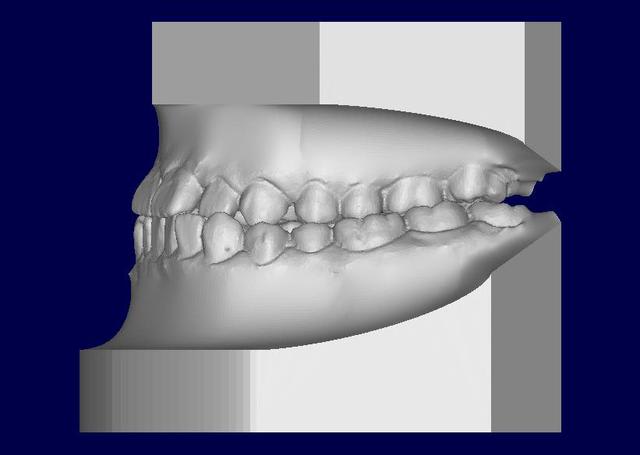

Ci joints photos, ceph, modeles.

Patient asiatique, 25 ans, consulte car il veut corriger son crossbite bite antérieur localisé aux latérales et son crossbite secteur 2/3. Il aimerait également corriger son apparence générale, son profil notamment.

Classe III squelettique et dentaire.